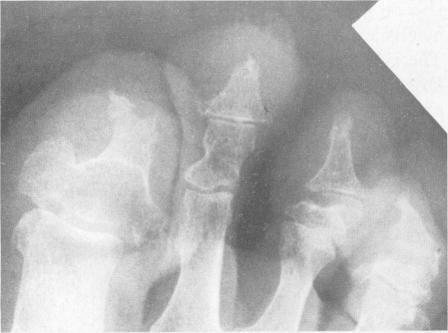

Herbert D A, Fessel W J

West J Med. 1981 Apr;134(4):354-7.